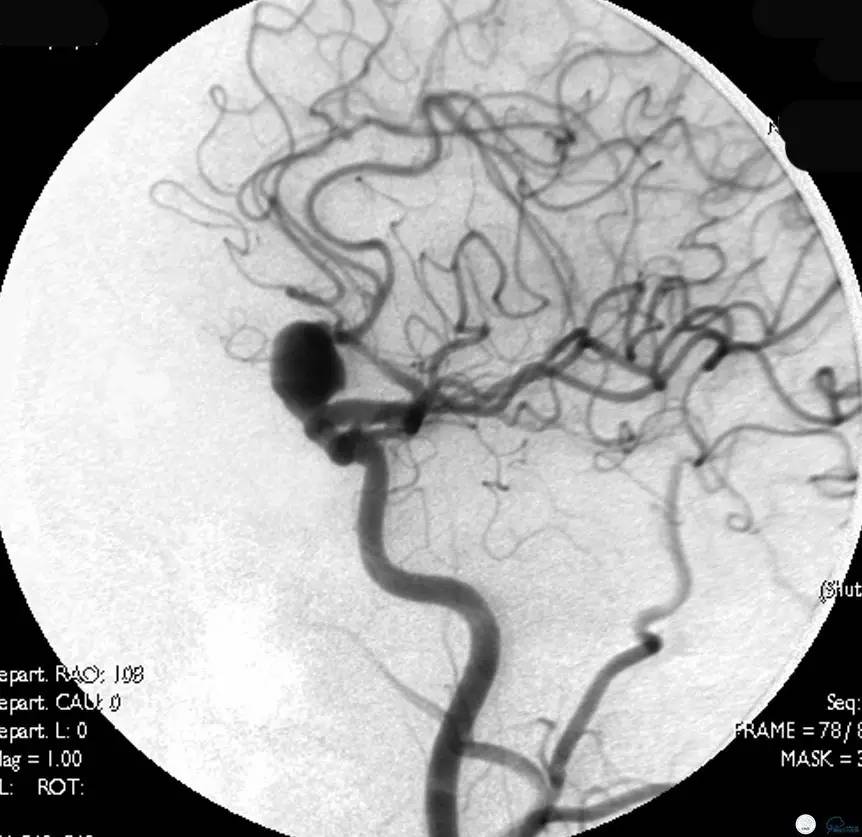

Case1 右ICA多发床突旁动脉瘤

术前VS术后即刻